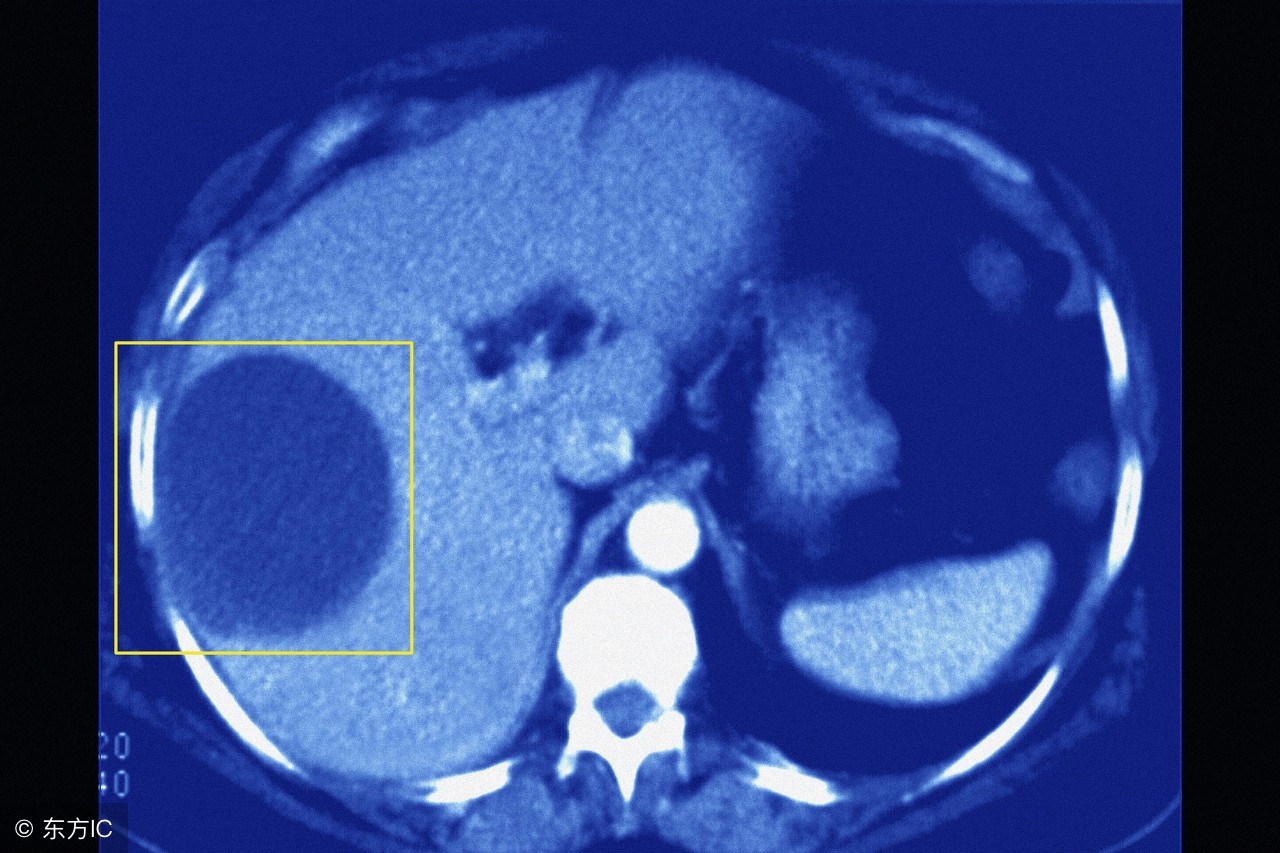

用通俗的话说,囊肿就是包了一包“水(液性东西)”的“囊状物”,囊,就是指的囊状、囊样、囊袋,一个囊袋里面包了水样的液性东西,这个液性东西可以是炎性物,可以是血性物,还可以是不明原因的液态物,这类东西包成一团,外面有包膜,如果摸,感觉是“软软的”,这就成了囊肿,所有这类囊性物,广义上都可以称之为“囊肿”,或者可以泛称为“囊性”病变,或者“囊样”病变。不过,从狭义上说,囊肿指的是一类良性疾病,比如肝囊肿,肾囊肿等,这类囊肿,有的是单发的,有的是多发的;有的是先天性的,有的则是后天继发的。比如,孤立性肾囊肿,先天性多囊肾等等。

用什么手段去区分呢?通常B超在大多数情况下可以诊断囊肿,比如肝囊肿,肾囊肿,但有的囊肿,它是单纯的囊肿还是真正意义的肿瘤,这个要综合B超、CT等影像学检查并对其分析(是否含有实性成分、影像表现特点等)、病史、查体等来综合判断。比如,B超发现卵巢有囊肿,你不能简单地说,这个肯定是良性的病变,没事,不用担心。其实卵巢的囊肿有不同的情况,你得结合具体情况来分析去判断,而不要简单地下结论。尽管在大多数情况是良性的病变,但也可能是卵巢恶性肿瘤的一种表现,卵巢癌也可能会有囊肿的表现。另外,卵巢的巧克力囊肿是一种较为特殊的“囊肿”,它本质上是卵巢子宫内膜异位症,也就是子宫内膜异位到卵巢,然后和子宫内膜一样,会随着月经周期而每个人月周期性剥脱出血,这些出血不能排出体外,积聚并包裹起来,由于这种陈旧性积血颜色起来像巧克力,这样就形成了所谓的巧克力囊肿,可不是真的长了巧克力哈。所以诊断这种卵巢囊肿,你得综合病史、临床表现、B超检查等来分析判断。而真正意义上的肿瘤,特别是恶性肿瘤,确诊要靠活检或手术病理检查。